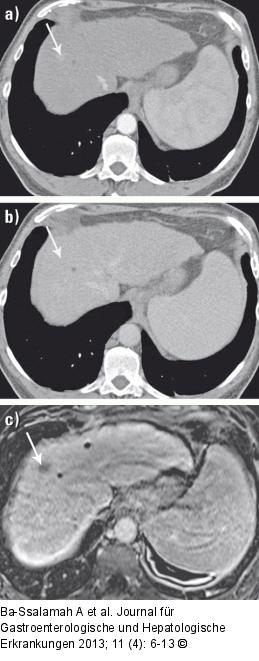

Abbildung 6a-c: MRT-Diagnostik KM-verstärkte MRT charakterisiert ein HCC besser als KM-verstärkte CT. (a) KM-verstärktes CT-Bild in der arteriellen Phase zeigt eine ca. 1 cm große, flaue hypervaskularisierte Läsion im rechten Leberlappen (Pfeil). (b) Im KM-verstärkten CT-Bild in der portalvenösen Phase ist die ca. 1 cm große, flaue hypervaskularisierte Läsion im rechten Leberlappen nicht erkennbar. Somit ist eine eindeutige Diagnose eines HCC (gegenüber einem dysplastischen Knoten) nicht möglich. (c) 20 Minuten nach Gabe von Gadoxetat zeigt die ca. 1 cm große Läsion im rechten Leberlappen ein eindeutiges Wash-out. Somit ist eine Differenzierung des HCC möglich. |

KM-verstärkte MRT charakterisiert ein HCC besser als KM-verstärkte CT. (a) KM-verstärktes CT-Bild in der arteriellen Phase zeigt eine ca. 1 cm große, flaue hypervaskularisierte Läsion im rechten Leberlappen (Pfeil). (b) Im KM-verstärkten CT-Bild in der portalvenösen Phase ist die ca. 1 cm große, flaue hypervaskularisierte Läsion im rechten Leberlappen nicht erkennbar. Somit ist eine eindeutige Diagnose eines HCC (gegenüber einem dysplastischen Knoten) nicht möglich. (c) 20 Minuten nach Gabe von Gadoxetat zeigt die ca. 1 cm große Läsion im rechten Leberlappen ein eindeutiges Wash-out. Somit ist eine Differenzierung des HCC möglich. |